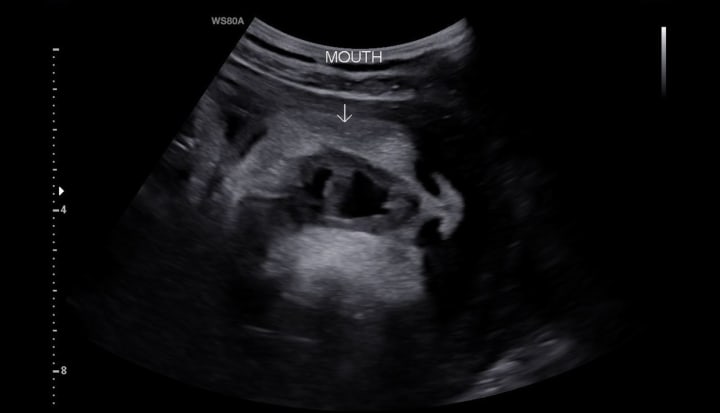

He missed out on seeing ultrasounds of our little baby kicking and yawning. He missed out on hearing his little heartbeat in the womb. I was alone to hear both the good news and the bad news.